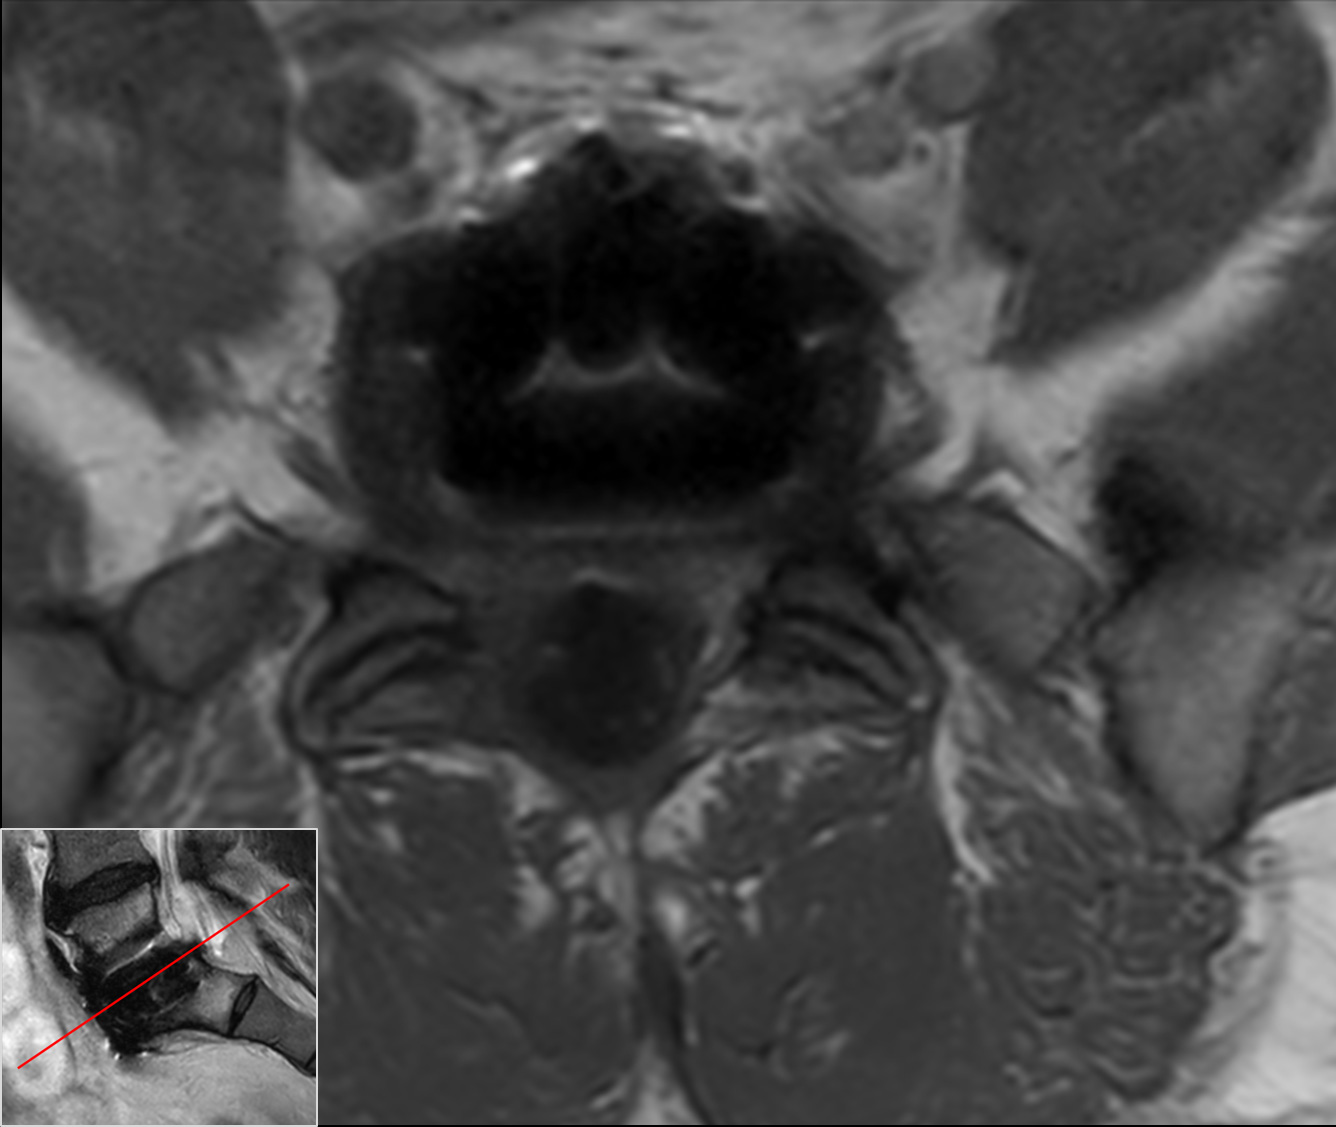

Axial T2w TSECompressed SENSE

Axial T1w TSECompressed SENSE